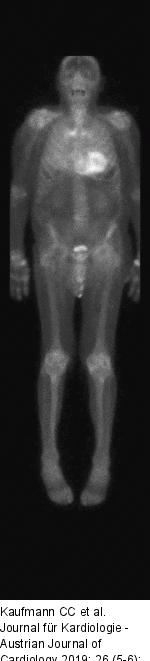

Abbildung 5: Amyloidose-Skelett-Szintigraphie Amyloidose-Skelett- Szintigraphie. Homogene Anreicherung des Tracers im Myokard, vereinbar mit dem Vorliegen einer ATTR-Amyloidose. |

Abbildung 5: Amyloidose-Skelett-Szintigraphie

Amyloidose-Skelett- Szintigraphie. Homogene Anreicherung des Tracers im Myokard, vereinbar mit dem Vorliegen einer ATTR-Amyloidose. |